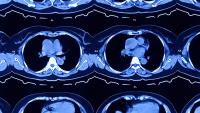

Radiologists play a critical role in the early detection, diagnosis, and even in the treatment of disease. Our radiologists are nationally-recognized experts who have a deep understanding of disease, often catching important details that may otherwise be overlooked.Â

When you choose Columbia Radiology, you're choosing to be affiliated with NewYork-Presbyterian Hospital, one of the top rated hospitals in the country. You'll have access to the most current technology and image-guided therapies along with radiologists and technicians who perform and interpret more than 800,000 procedures and scans each year. Our commitment to expert, personal care means that your radiologist will partner with your physician and become an integral part of your healthcare team.